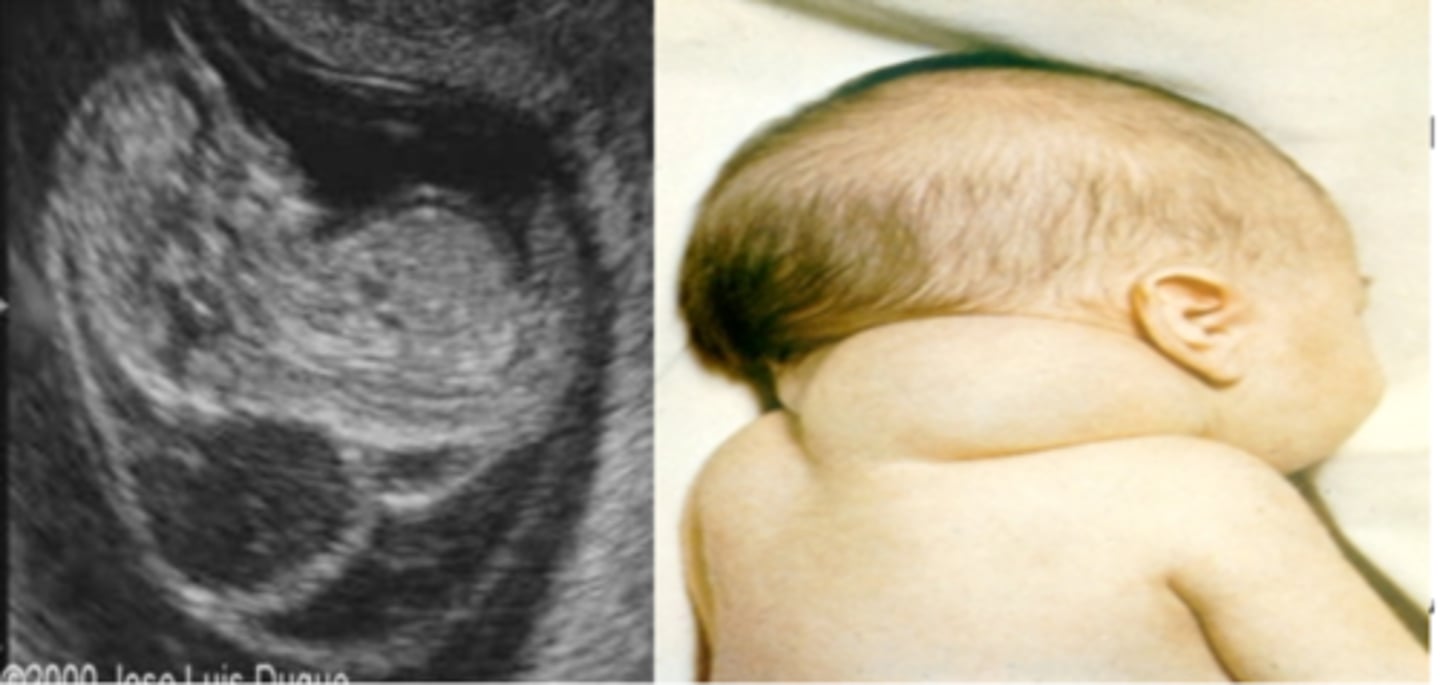

What is a cystic hygroma?

Large fluid-filled swellings involving jugular lymph sacs that fail to connect to lymphatic vessels.

<p>Large fluid-filled swellings involving jugular lymph sacs that fail to connect to lymphatic vessels.</p>